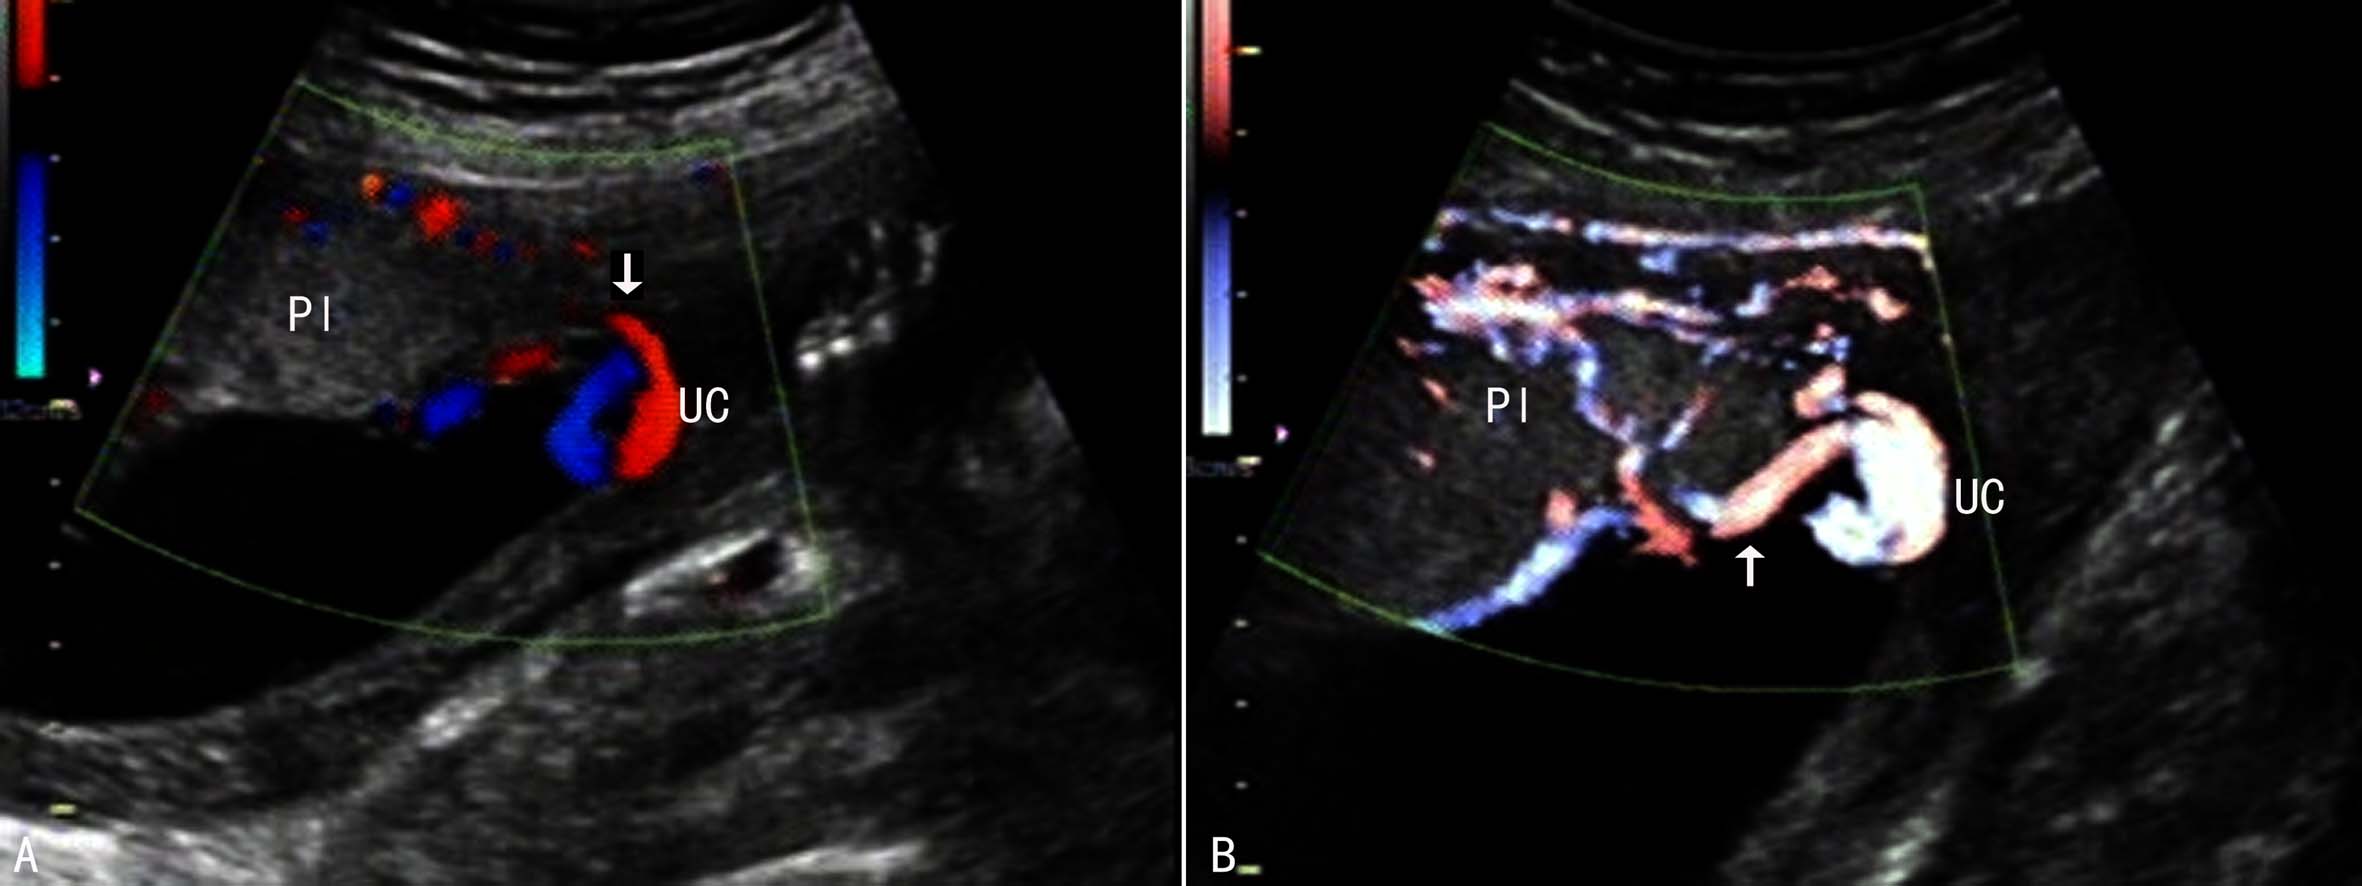

脐带边缘附着时超声显像检查可以发现脐带附着于胎盘边缘,一般以距边缘≤2cm为诊断标准;脐带进入胎盘前脐带血管维持正常的绞合状态,脐带结构和血流多不受影响(图2)。当脐带血管进入胎盘以前已经失去正常的绞合状态则形成脐带帆状附着,脐带血管分离后其周围无胎盘组织显示。彩色多普勒血流显像及三维超声显像检查可以显示脐带附着处的血流及其空间结构,更有利于显示脐带血管与胎盘的关系,有利于显示脐带帆状附着(图3)。

在晚期妊娠过程中,由于羊水量相对减少,胎体在羊膜腔内占据的空间比较大,常常影响脐带根部的显示和胎盘的完整显示;在中期妊娠过程中,羊水量相对较多,尤其是能够通过孕妇体位的改变将胎体和胎盘子体面分开,在羊水无回声区内多可清晰地显示胎盘回声,显示脐带根部与胎盘的关系即可明确脐带的附着部位,观察脐带根部的血管回声状况可以辨别脐带边缘附着(图2)和脐带帆状附着(图3)。彩色多普勒血流显像可以明确地显示脐带血管及血管与胎盘的关系,多普勒能量图显示不受血流方向和速度的影响,对脐带血管和胎盘血管的显示更有利,对边缘附着和帆状附着的诊断会更有意义。

图3脐带帆状附着